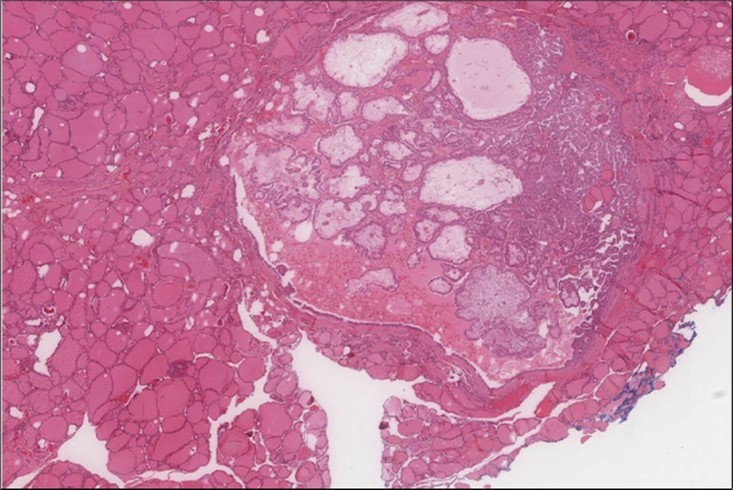

When diagnosing thyroid swelling, imaging studies have been helpful in differentiating malignant from benign tumors with US being used as an initial evaluation tool when assessing thyroid nodules. Tumors are categorized based on composition, echogenicity, shape, margin and echogenic foci into added scores determined by the TI-RADS system, which determines the need for FNA 13. Other imaging modalities include MRI and CT. However; radiological assessment does not distinguish between the types of thyroid cancer, and therefore FNA and biopsy are of crucial importance 3, 6. On a pathologic sample, LMS appears as spindled eosinophilic cells with elongated blunt-ended or cigar-like nuclei arranged in fascicles 2, 7 (Figure 1, Figure 2, Figure 3). Despite the unique microscopic morphology, LMS cannot be distinguished from other spindle cell tumors such as spindle cell variant of medullary thyroid cancer, anaplastic thyroid

Figure 1.Left thyroid Low power of the thyroid gland showing complete replacement of the thyroid by the neoplastic cells (H&E, ×4).

Figure 2.Left thyroid On a Higher power, few thyroid follicles are noted and the lesion is composed of spindle cells with sweeping fascicles (H&E, ×200).

cancer, or other metastatic tumors without further testing with genetic or molecular studies 3, 7. Immunohistochemical testing plays a vital role in differentiating LMS from such similar tumors as it stains positive for vimentin and smooth muscle actin (SMA), and is variably positive for HHF35, desmin (50%-100%), and H-caldesmon 3, 6. Moreover, there were no reported cases where thyroid LMS stained positive for thyroglobulin, cytokeratin, calcitonin, chromogranin, or protein S100 3. Our patient’s left thyroid biopsy showed the characteristic microscopic features and was positive for SMA, desmin, caldesmon, P63 with patchy EMA (Figure 1, Figure 2, Figure 3, Figure 4) as well as her liver biopsy (Figure 5, Figure 6, Figure 7); whereas her right thyroid showed clear papillary thyroid cancer cell features (Figure 8, Figure 9).